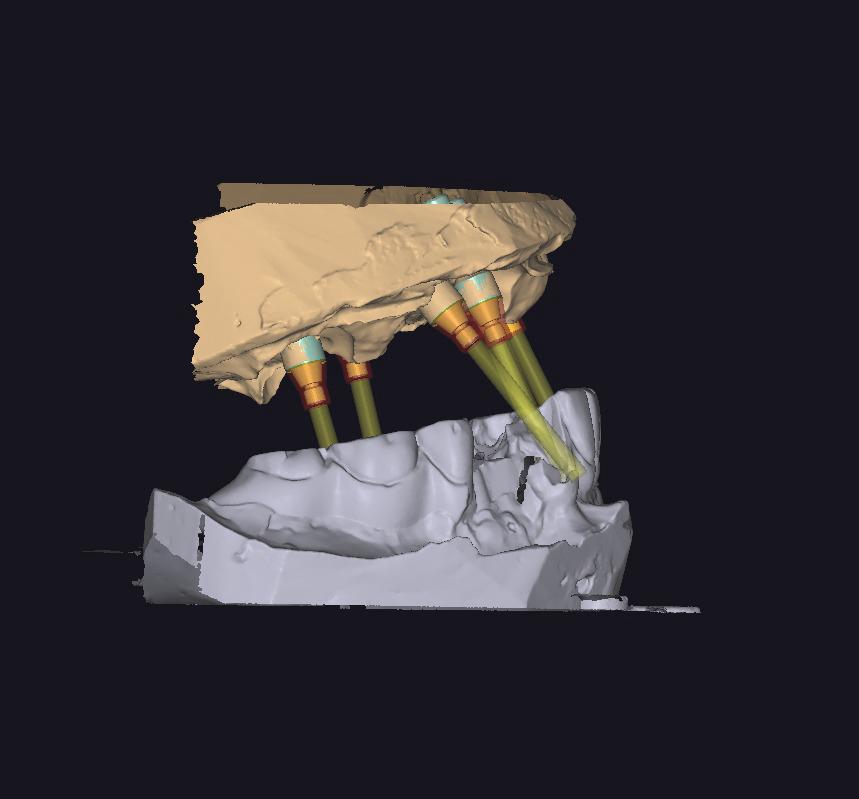

CAD CAM CERRAHI PLAK

IMPLANT VİDASI